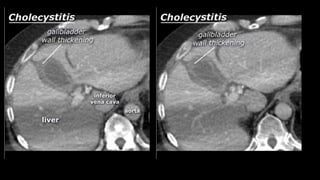

• Cholecystitis

• A complication of bile stones is an infected

gallbladder or cholecystitis. Cholecystitis

rarely occurs in the absence of bile stones.

Ultrasound is also best suited to diagnose

cholecystitis. Ultrasound improves the

visibility of the bile stones, and gallbladder

compressibility can be evaluated (dynamic

examination). Absent compressibility

constitutes a key characteristic of

cholecystitis (see abdominal ultrasound

class). Other characteristics of cholecystitis

on CT include gallbladder wall thickening

and infiltration of the fat surrounding the

gallbladder. A common complication of

cholecystitis is gallbladder perforation,

where bile leaks into the abdominal cavity

(biloma).

• Cholecystitis • Acomplication of bile stones is an infected gallbladder or cholecystitis. Cholecystitis rarely occurs in the absence of bile stones. Ultrasound is also best suited to diagnose cholecystitis. Ultrasound improves the visibility of the bile stones, and gallbladder compressibility can be evaluated (dynamic examination). Absent compressibility constitutes a key characteristic of cholecystitis (see abdominal ultrasound class). Other characteristics of cholecystitis on CT include gallbladder wall thickening and infiltration of the fat surrounding the gallbladder. A common complication of cholecystitis is gallbladder perforation, where bile leaks into the abdominal cavity (biloma).